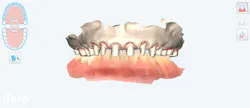

Smile design planning with the use of Exocad (figures 8 and 9) revealed a reduced vertical dimension of occlusion (VDO) secondary to posterior tooth loss, attrition, and condylar remodeling from chronic bruxism. To address this, the patient’s VDO was incrementally increased by 3.5 mm, restoring esthetic relationships and lip support. This approach minimized the need for crown lengthening or endodontic intervention and allowed conservation of natural tooth structure.

A digitally printed wax-up and tooth reduction guides facilitated minimally invasive preparations while ensuring restorative thickness. Gingival architecture was refined using a diode laser for optimal contour, hemostasis, and patient comfort. The iTero Lumina single-scan protocol streamlined data acquisition, enhancing precision for both provisional and definitive restorations.